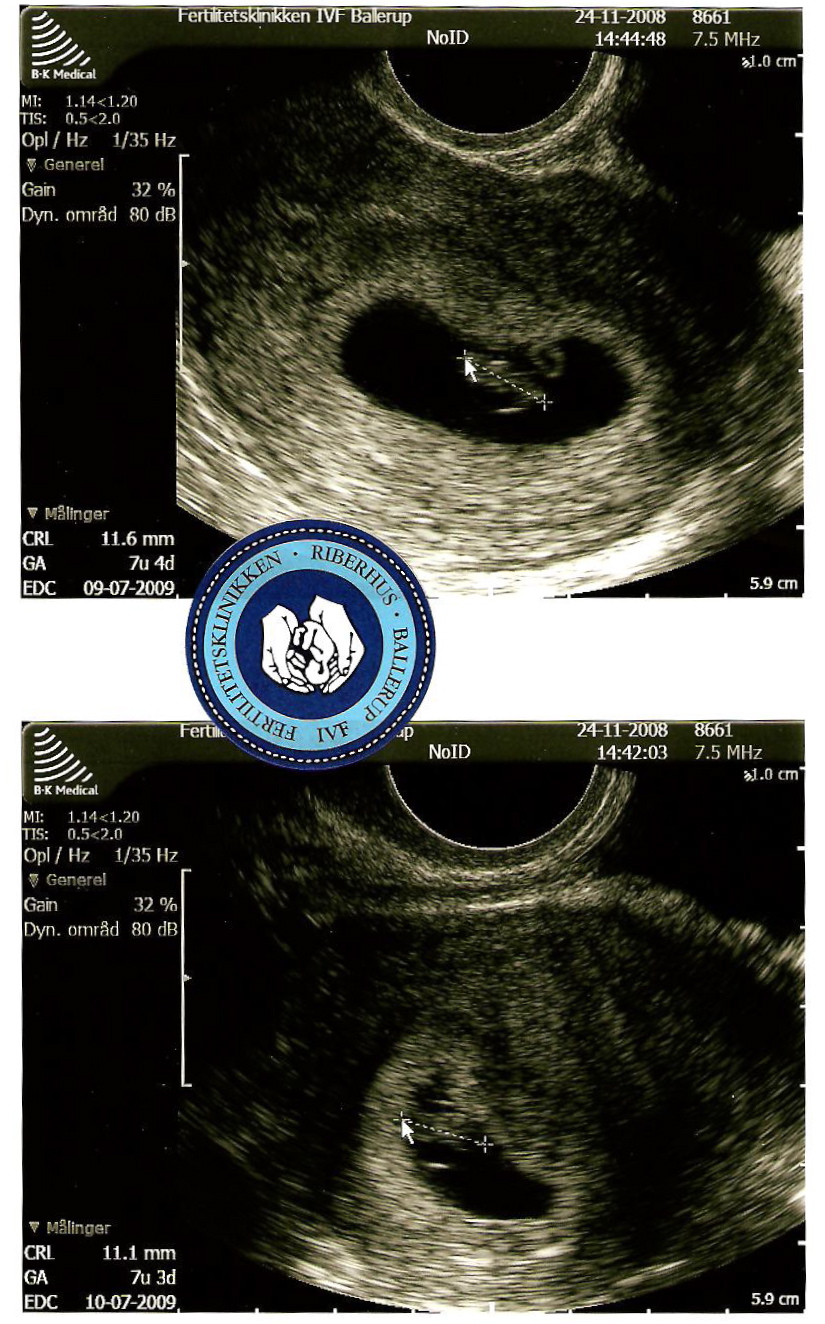

Det føles som et mirakel. Der ER en lillebitte baby i min mave! Vi så hende/ham for første gang i dag på scanningen. Og mest fantastisk: Vi så det lille bitte hjerte slå! Det var så fantastisk. Tårerne trillede ned af mine kinder, jeg krammede min kærestes hånd – jeg kunne være blevet liggende og bare kigget på det lille myr og det lille bankende hjerte.

Vores baby er 11,6 mm fra hoved til ende.